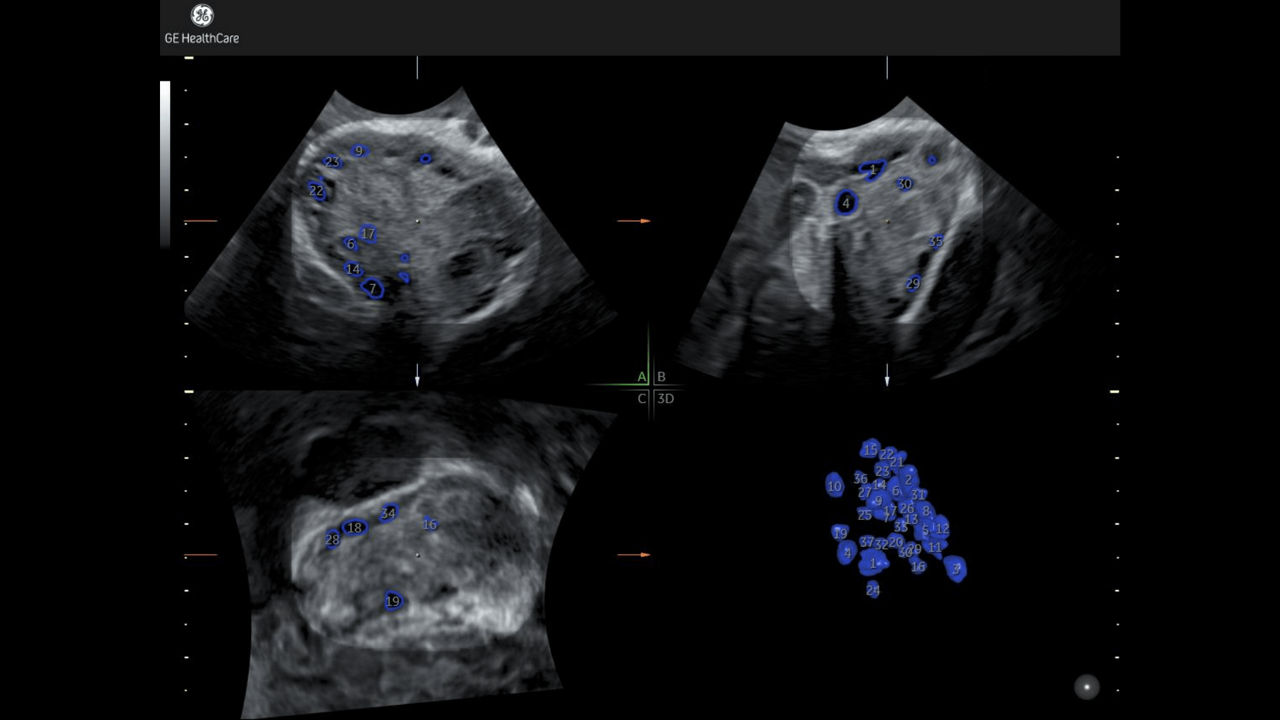

SonoAVC™ follicle with Auto Caliper

Automate follicle counts in 2D or 3D.

Developed by: GE HealthCare - Voluson™

1_sono-avc-follicle-with-auto-caliper